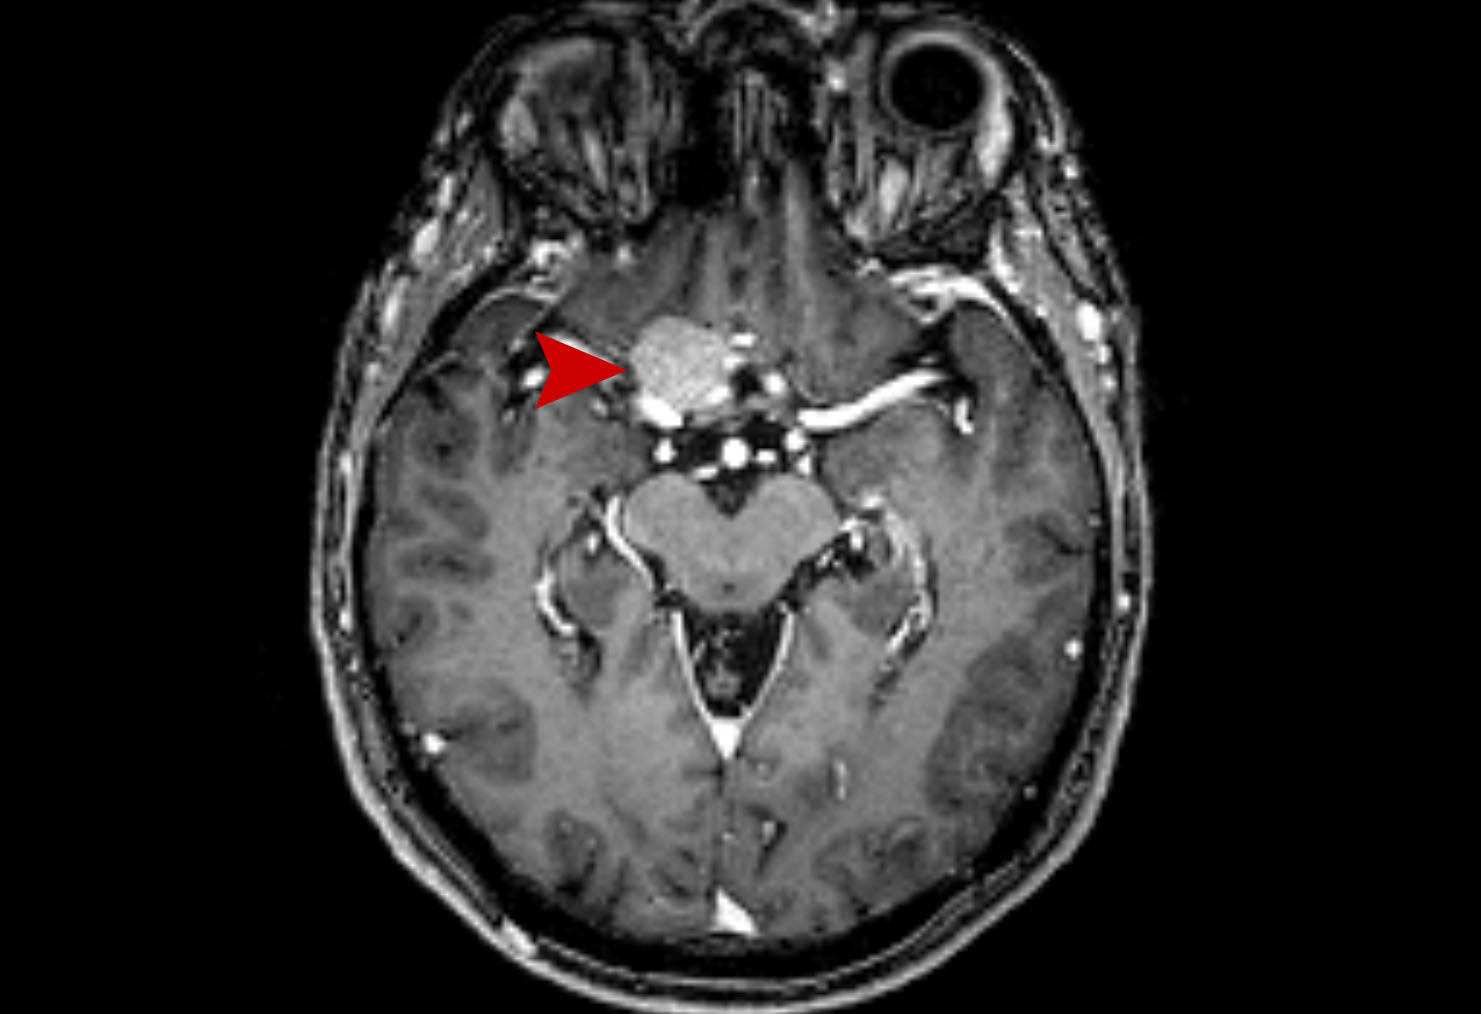

Μεταστατικός Καρκίνος Πνεύμονα στον Εγκέφαλο Θεραπεία με CyberKnife #25

Άρρεν 58 ετών με ευμεγέθη εγκεφαλική μετάσταση από Ca πνεύμονος κατά το αριστερό εγκεφαλικό σκέλος…